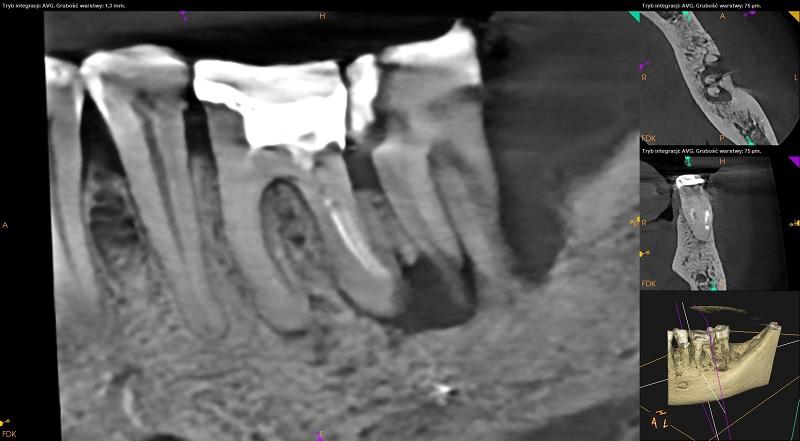

Ząb 37 – bez znamion leczenia kanałowego. W tkankach korzenia widoczna szczelina złamania.

Rozległy zanik tkanki kostnej wokół korzeni zęba obejmujący blaszkę zbitą po stronie policzkowej.

Ząb 36 – przeleczony kanałowo. W części przywierzchołkowej kanałów materiał wypełniający niewidoczny (kanały mezialne – 6mm, dystalny - 3mm). W kanale mezialnym policzkowym podejrzenie złamanego narzędzia. W korzeniu dystalnym via falsa.

Wokół wierzchołka korzenia mezialnego ognisko rozrzedzenia struktury kostnej (1,5mm x 2,5mm).

Wierzchołek korzenia dystalnego objęty zanikiem kostnym.